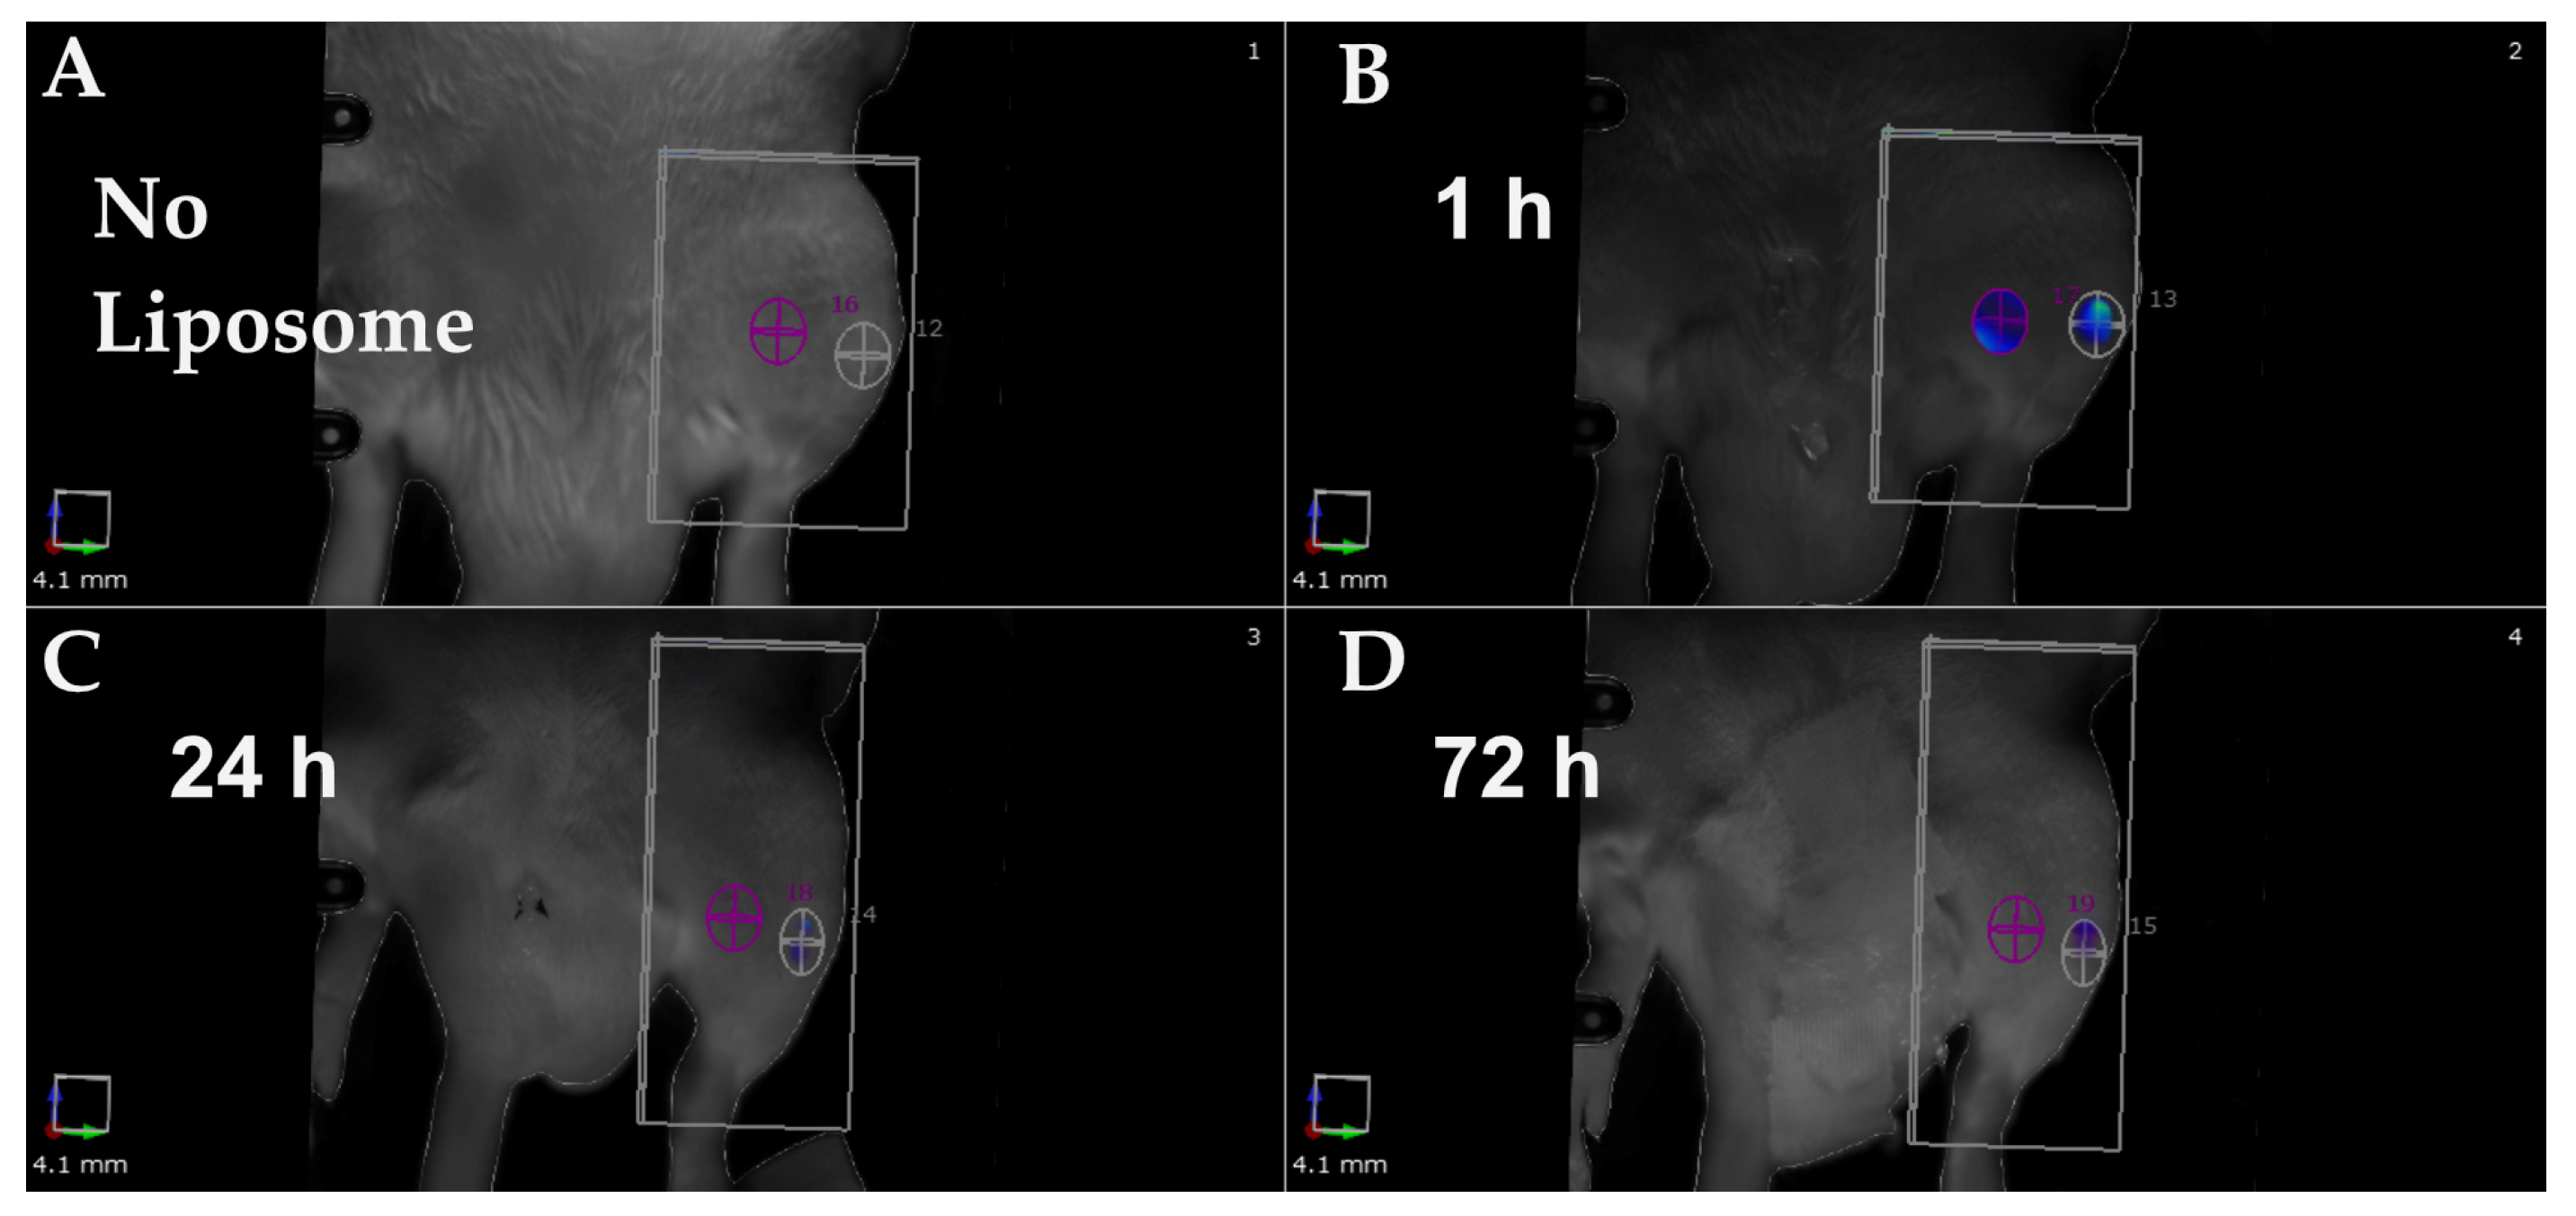

2.2. In Vivo Evaluation of α-MSH-SM-Liposomes

4.6. Imaging of α-MSH-SM-Liposomes